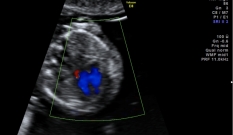

Se, por alguma razão, fosse feito um ultrassom vaginal de alta resolução, seria possível observar muitos detalhes do feto, como o cristalino dentro dos olhos e as válvulas do coração, e contar seus dedos quando abre a mão.